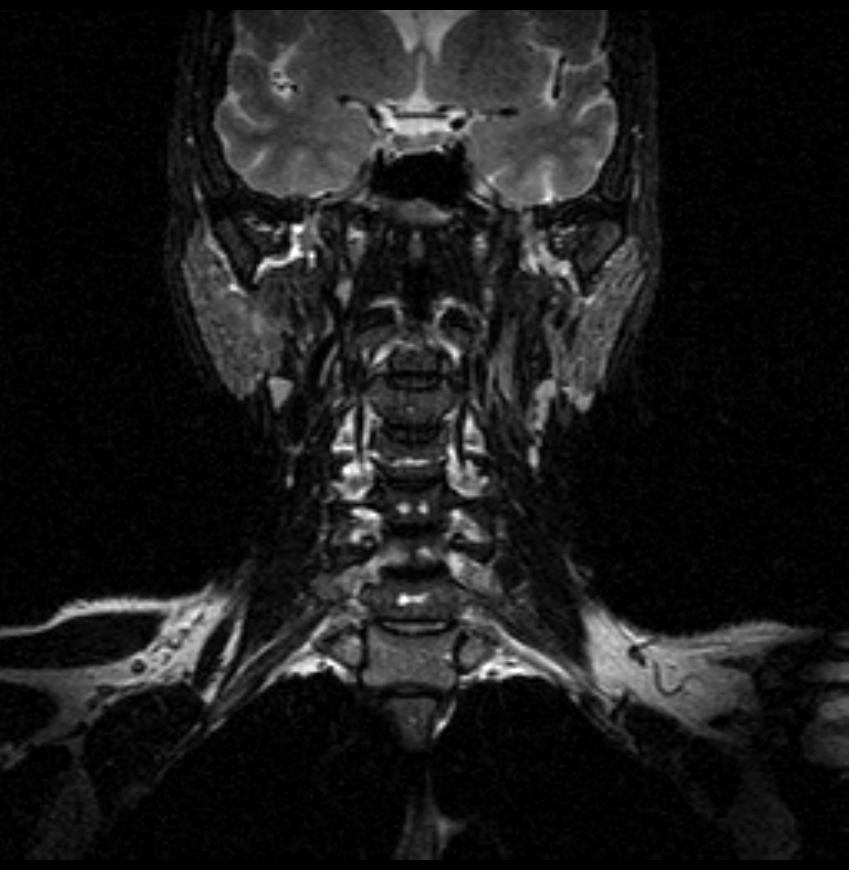

06.06.2011 МРТ - головы и шеи.

Пацентка 36 лет, с жалобами на припухлось в околоушной области справа.

В глубокой доле  правой околоушной железы  на фоне неизмененной паренхимы зона  гетерогенного по Т2, гипоинтенсивного по Т1  с единичными гиперинтенсивными включениями.При контрастировании- накопление контраста диффузное неоднородное и по периферии.Рискну предположить злокачественное образование ( аденокарцинома) с низкой степенью злокачественности( есть капсула, экспансивный рост).Сильно не расстреливайте.

Проблема в том, что перед челюстно-лицевым хирургом стоит распространенность любого объемного процесса, в данном случае все упирается в возмможную травму лицевого нерва и конечно же с дальнейшим его парезом, а ведь женщина  еще молодая. Образование имеет тонкостенную оболочку, по структуре неоднородно, с наличием кальцината, при этом МР-сигнал от окружающих анатомических структур(как костных так и мышечных) не изменен, т.е. об инфильтративном росте речи не идет, в какой то степени доброкачественное. В конкретном случае лицевой нерв с ретромандибулярной веной просто несколько оттеснен.

По гистологии аденома околоушной слюнной железы, но после удаления пока сохраняется парез лицевой мускулатуры, возможно временный.